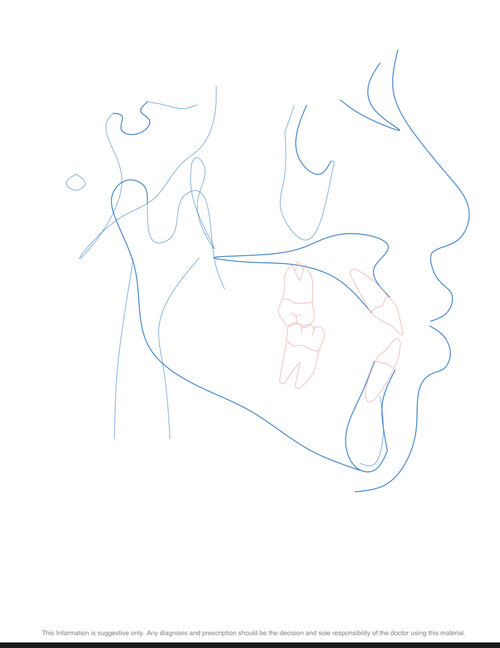

i have a lefort1+sarpe+braces planned for my bite problems and ive been told i need a double jaw surgery and genioplasty which isnt what the surgeon thought i needed in the consultation ive been at.

Other than that,what procedures should i be looking at, im willing to do any